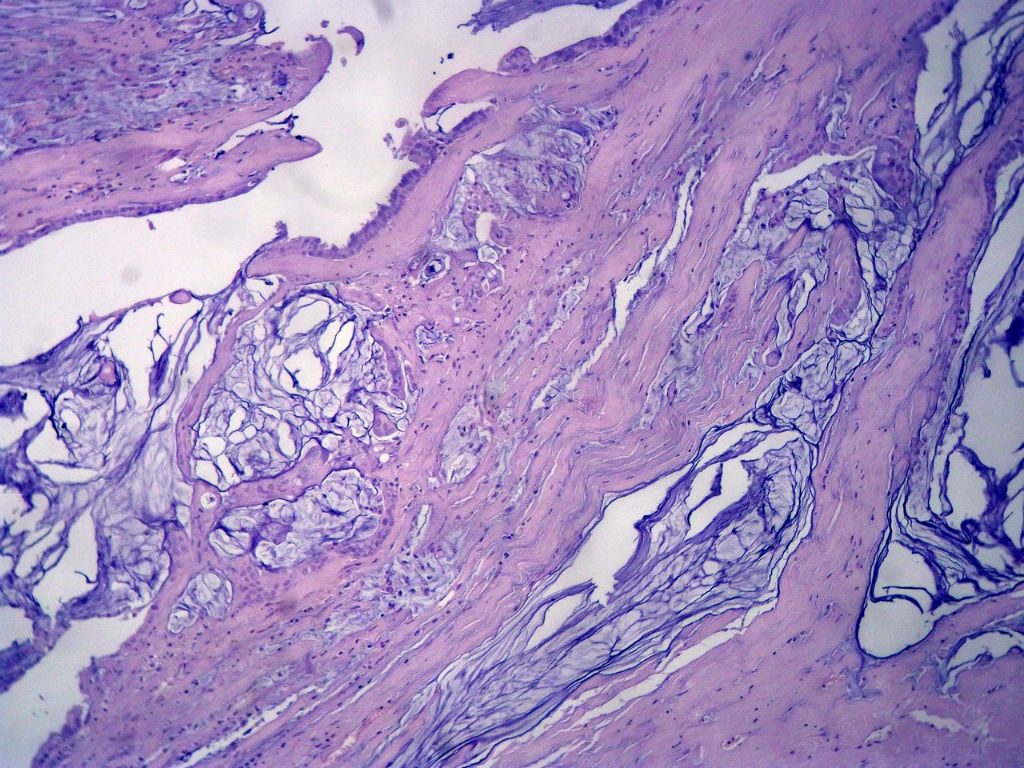

• 女,80岁,阑尾区肿块。图4

图4

送检为不规则组织多块,粘滑,解剖结构辨认不清。术中探查双侧卵巢无异常。

阑尾粘液性肿瘤,癌的可能性大

粘液长在肌层,而且漂浮着可疑上皮细胞,最大可能粘液腺癌。